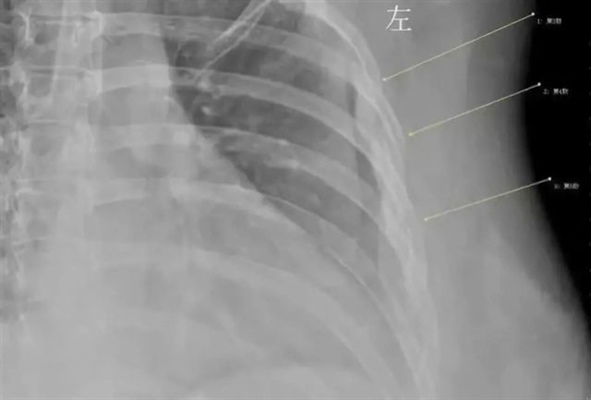

Sau khi chụp X-quang, bác sĩ của Han phát hiện ra rằng nguyên nhân gây ra cơn đau ngực của cô là do gãy xương sườn thứ ba, thứ tư, thứ năm vì ho quá dữ dội. Trong quá trình tìm hiểu căn nguyên, Han tiết lộ thêm rằng mình đã uống cà phê như nước lã và dùng hơn 10 tách mỗi ngày trong hơn 7 năm qua.

Xương của cô gái 30 tuổi mỏng tới nỗi gãy khi ho

Han đã trải qua một cuộc kiểm tra mật độ khoáng của xương và bác sĩ cho biết xương của cô giống với xương của một người già 60 tuổi. Tệ hơn nữa, Han biết được mình đang trên con đường bị loãng xương.